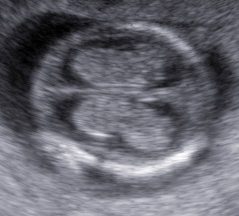

Lesiones cerebrales

En este resúmen gráfico se incluye la mayor parte de las lesiones cerebrales congénitas visibles en vida fetal; los cortes transversales expuestos aquí son insuficientes para algunas de ellas y los hallazgos pueden modificarse en el tiempo, usualmente manifestando mayor número de elementos anómalos. Muy pocas condiciones mejoran con el tiempo

Tomado de HN Xie et al. Using deep learning algorithms to classify fetal brain ultrasound images as normal or abnormal. Ultrasound Obstet Gynecol